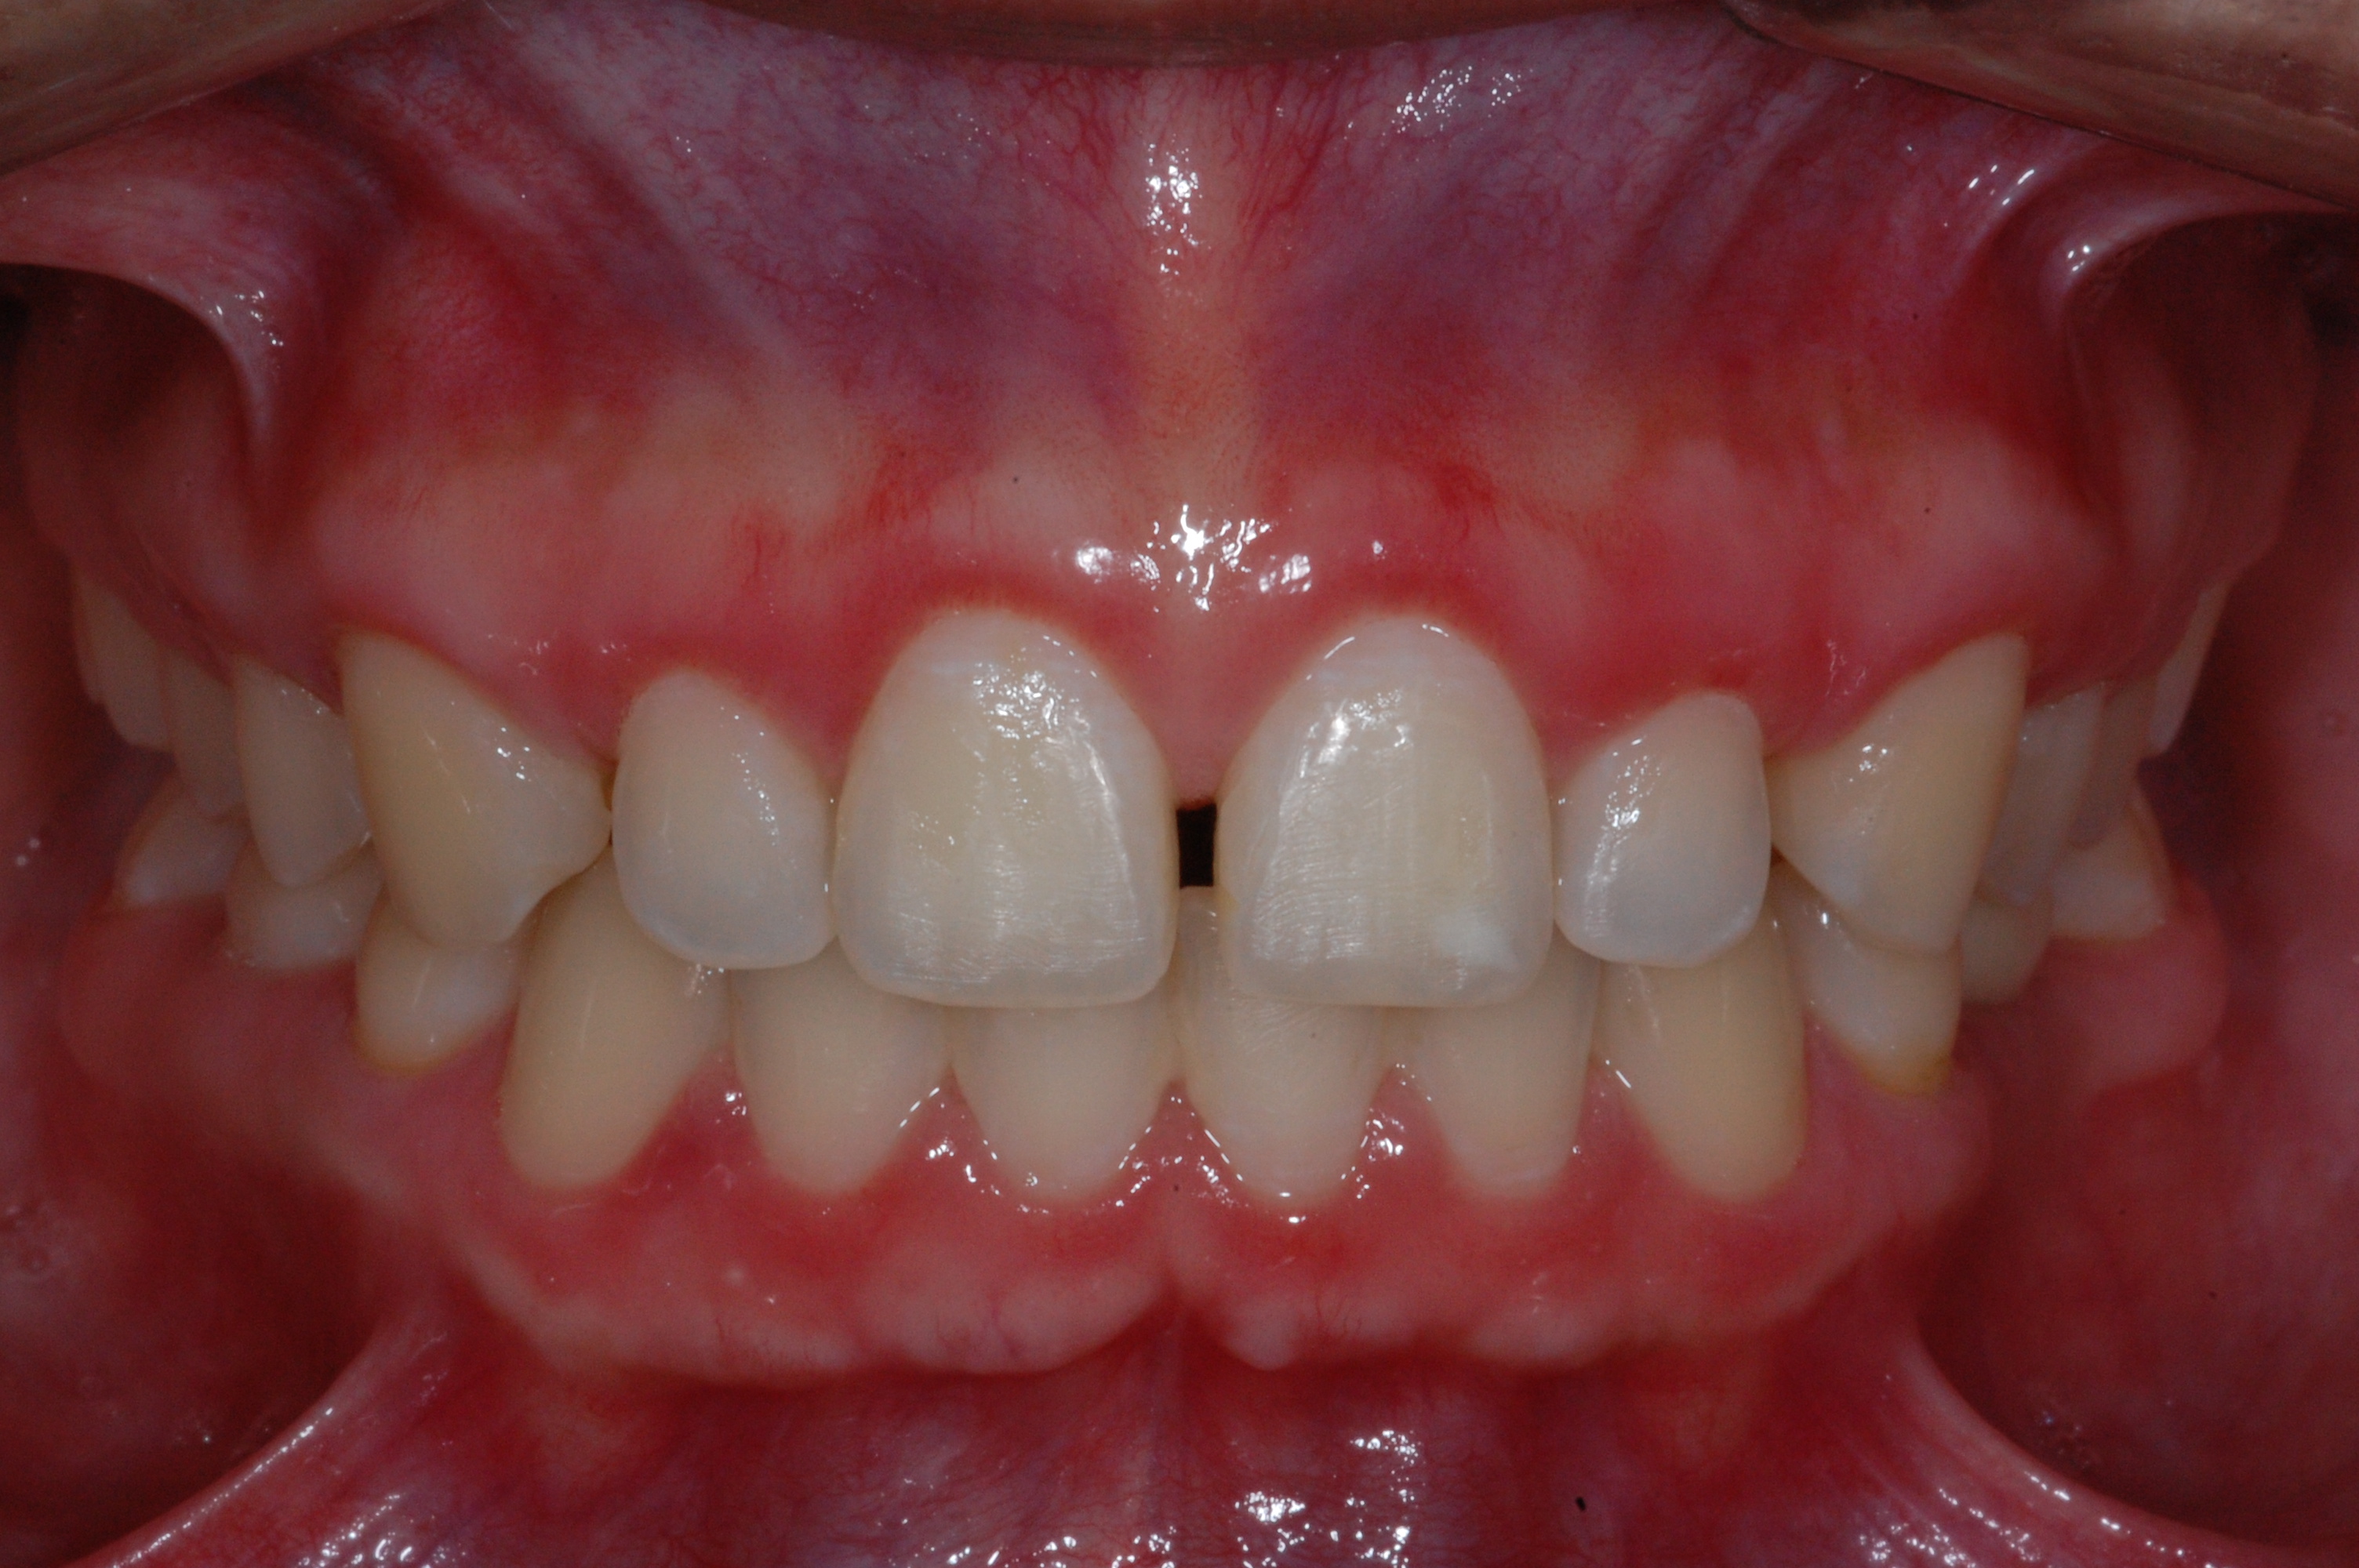

The presence of diastema, between anterior teeth, distorts a pleasing smile by concentrating the observer’s attention on the spaces. The patient’s needs and expectations must be considered in the process of treatment planning to ensure satisfaction with the treatment outcomes. There are many forms of therapy that can be used for diastema closure. A carefully developed diagnosis, which includes a determination of the causal elements and advanced treatment planning, allows the most appropriate treatment to be selected for each case. The aim of this paper is present a multidisciplinary approach as a solution to multiple diastemas in the anterior region using gingival tissue recontouring and direct adhesive restorations, with minimum wear of the dental structure, after the orthodontic intervention discussing the minimal intervention to obtain imperceptive and aesthetic final restoration. Thirty-six months after the treatment was carried out, the final aesthetic was maintained with all dental element details and gingival tissue harmony, without recurrence of periodontal pockets and the preservation of the tooth color and shape.